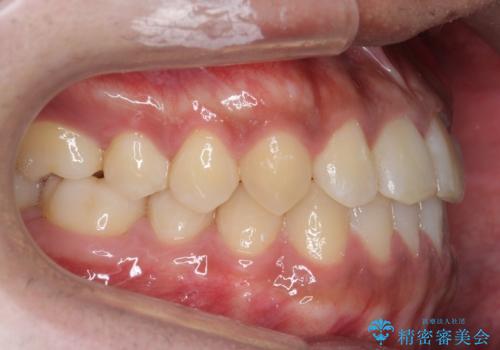

骨格性の受け口の矯正 部分ワイヤーで上の前歯を前に、 マウスピースで下の前歯を後ろに。

- 受け口を主訴に来院。

前歯のかみ合わせが逆になり上の前歯が奥に入っていました。

骨格性の受け口だったため、矯正用のミニスクリューを用いて、下の前歯をしっかり内側に入れました。

前歯を前に乗り越えさせるのは、ワイヤー矯正が一番早く歯に負担がかかりにくいです。

また、下顎はミニスクリューからマウスピースにゴムをかけて、下の歯並びが前に出ないようにして並べています。